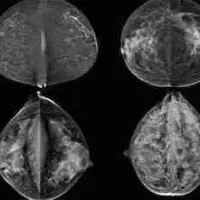

A large study in Japan finds improved rates of detection for breast cancer in women when ultrasound was added to standard mammography tests in breast screening. In addition to accurately detecting more cases of breast cancer, the combo method increased detection rate of early cancers, according to the results published in The Lancet.

Early detection and treatment is critically important for reducing deaths from the disease, and many developed countries have implemented mammography screening programmes for the women who are most at risk. In Asia, breast cancer tends to present at an earlier age than in Europe or the US, and Asian women have denser breast tissue, both of which are known to reduce the accuracy of mammography. As such, detection using standard mammography screening based on European and U.S. practice might miss cases of breast cancer in Asian countries.

Prof. Noriaki Ohuchi, PhD, Tohoku University Graduate School of Medicine (Miyagi, Japan) and colleagues recruited more than 70,000 women in Japan aged between 40 and 49 to participate in the J-START trial. Half were offered the usual mammography screening (control group), and half were offered ultrasound testing in addition to mammography (intervention group), with two screening sessions taking place over two years. The research team reported these key findings:

- Sensitivity, or correct identification of cancer, was significantly higher in the intervention group (91 percent) than in the control group (77 percent);

- More cancers were detected in the intervention group than in the control group (184 vs. 117) and were more frequently stage 0 and 1 (144 vs. 79);

- 18 interval cancers were detected in the intervention group compared with 35 in the control group.

The lower rate of interval cancers — which appear after a negative test result between scheduled rounds of screening — in the intervention group led researchers to conclude that adding ultrasound to mammography screening detected additional cancers, compared to mammography alone.